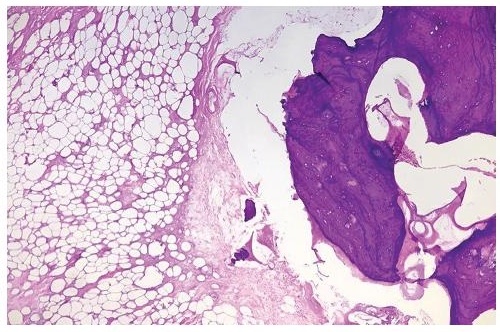

Gross examination showed yellow to cream/yellow, ovoid, fibrofatty to firm tissue with cream/white to cream/yellow smooth, glistening cut sections, with patchy areas of calcifications and fibrosis. Histopathologic examination showed mature adipose tissue with admixed mature lamellar bone (Figure 1) and areas with hyaline cartilage undergoing ossification (Figure 2). The adipocytes were monotonous and monomorphic. There was no nuclear atypia, lipoblasts, mitotic activity, or necrosis seen. The case was signed out as osteolipoma.

Figure 2. Mature adipose tissue with hyaline cartilage undergoing ossification (Hematoxylin & Eosin, 40x).